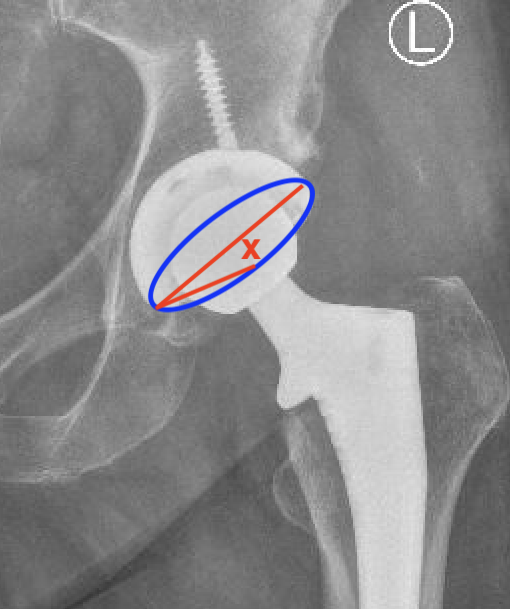

2. Acetabular Version

Xray

Difficult to measure on xray

Methods for measuring cup anteversion on xray PDF

CT scan

Altered by pelvic tilt